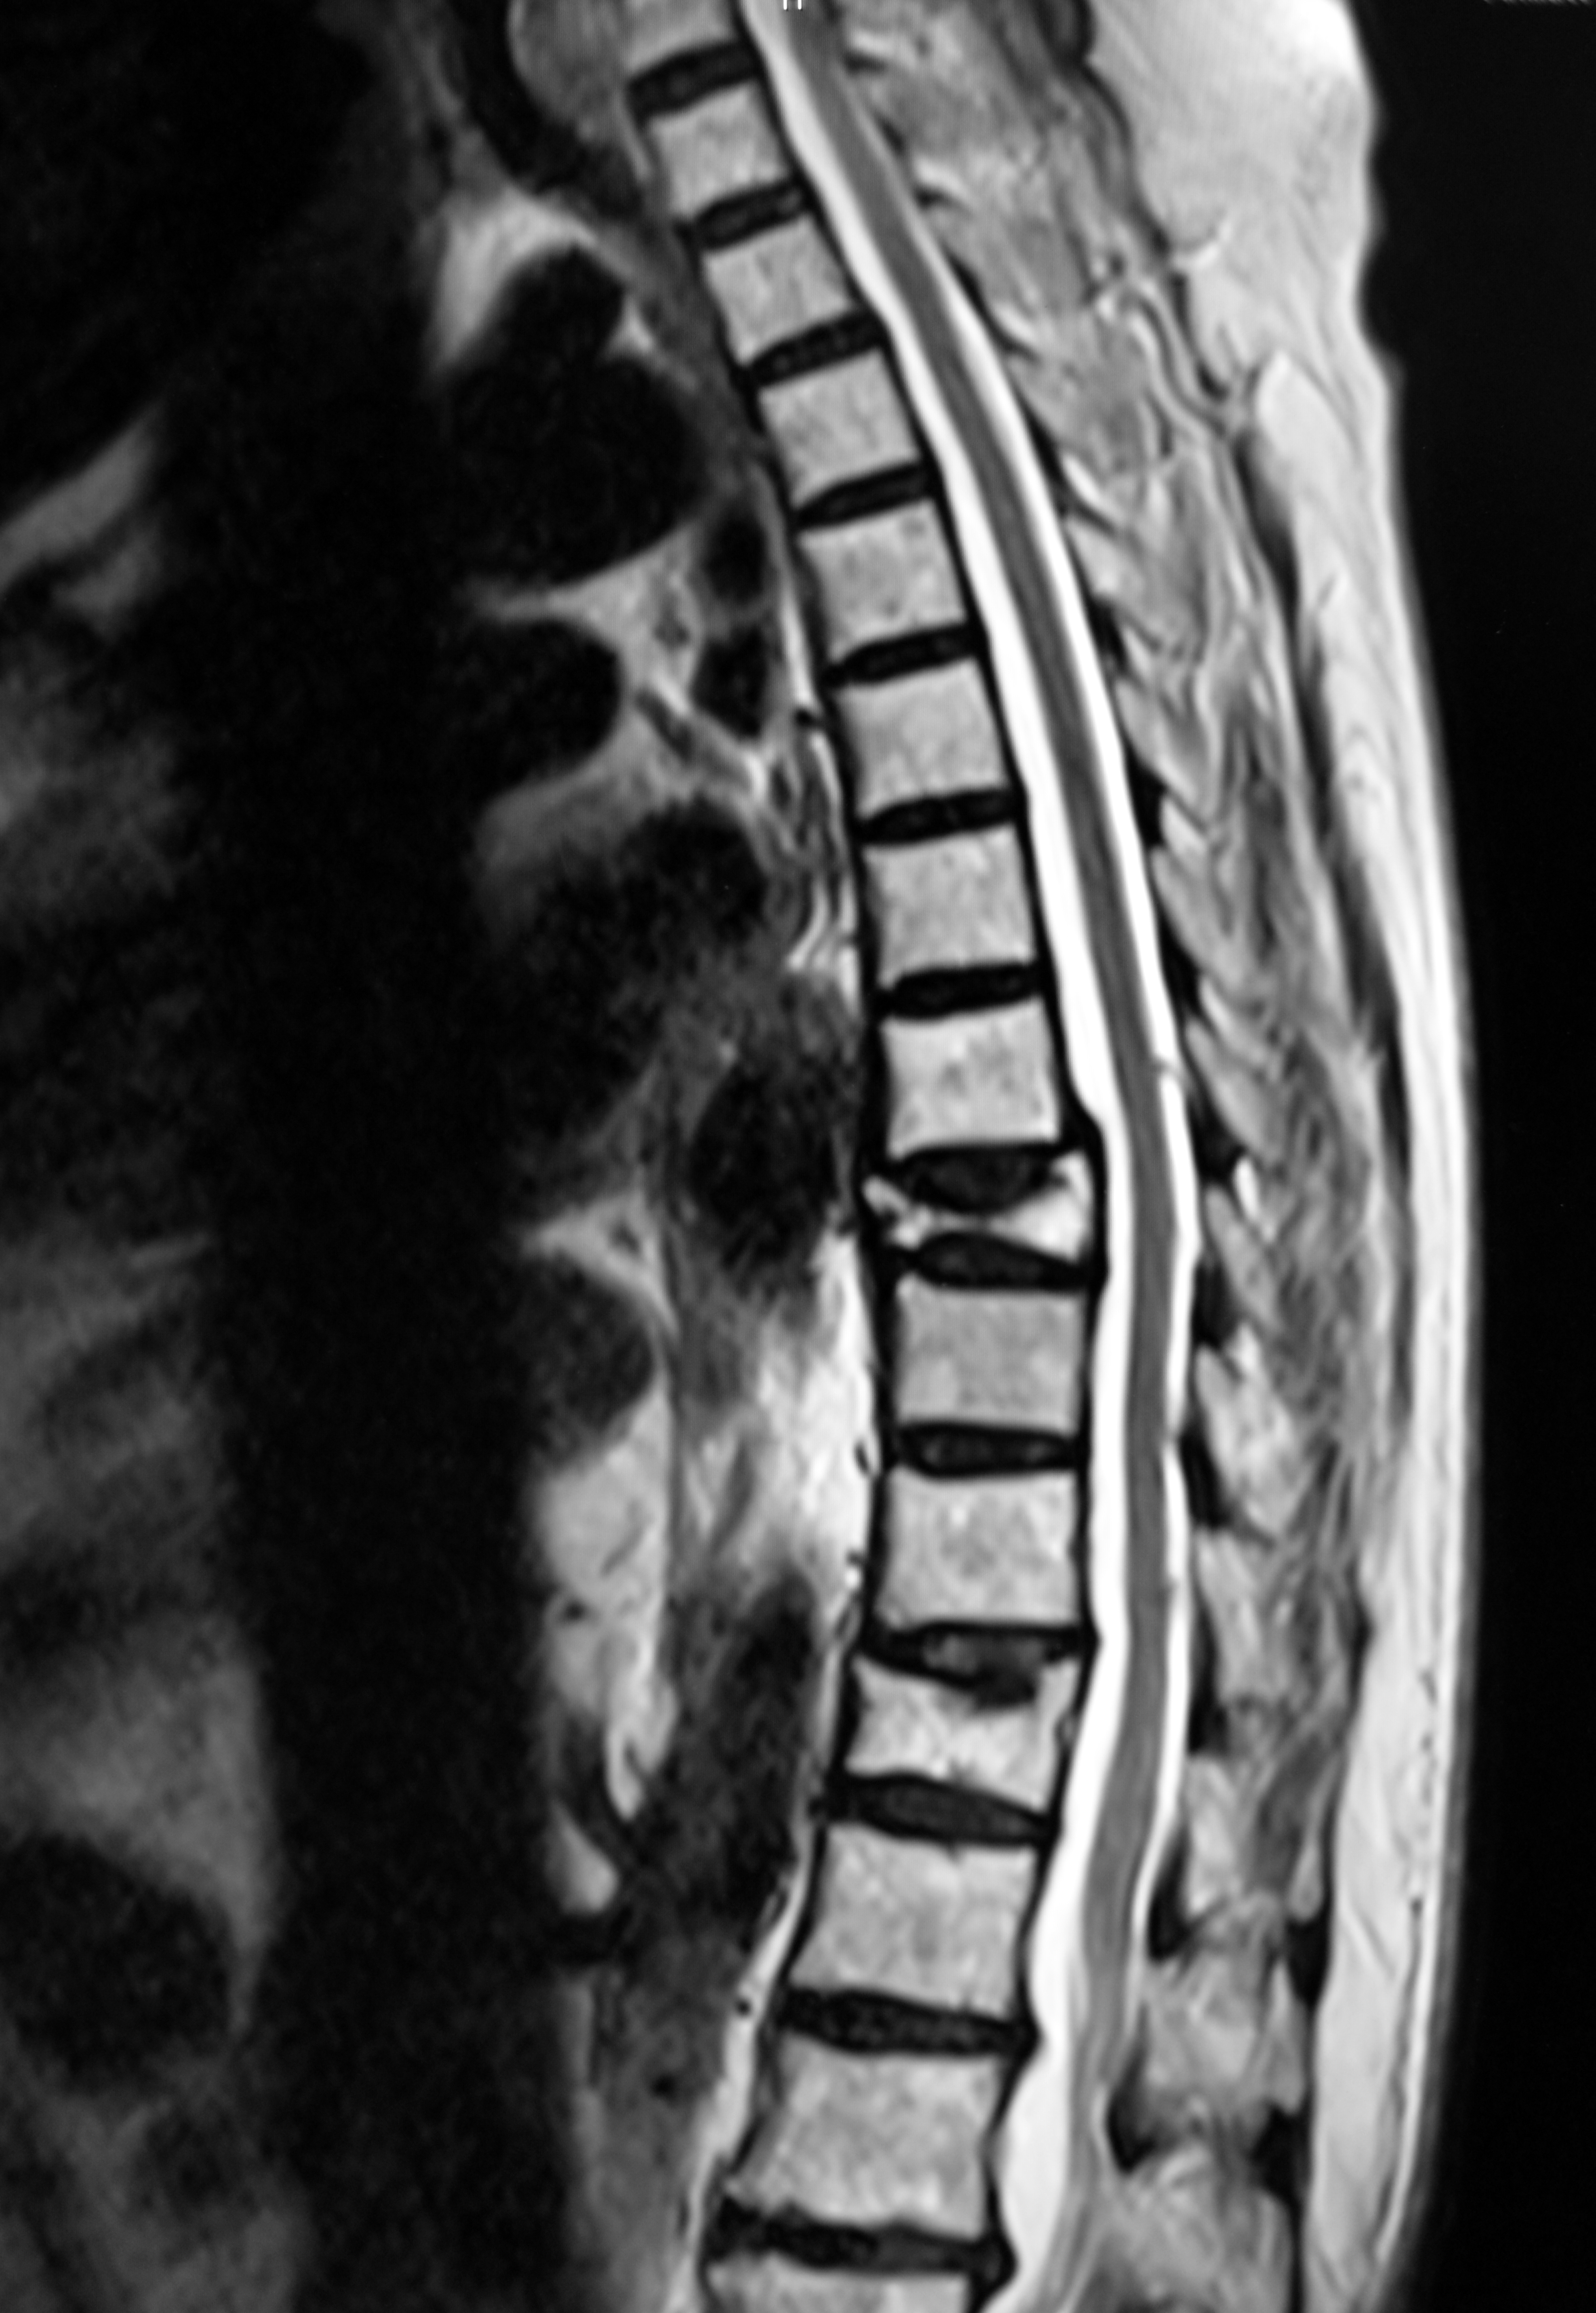

Osteoporosis is characterised by thin, fragile bones and may result in minimal trauma fractures of the spine bones (vertebrae). They can cause severe pain and disability. Vertebroplasty involves injecting medical-grade cement into a fractured vertebra through a needle, under light sedation or general anaesthesia. The cement hardens in the bone space to form an internal cast. This procedure has been widely used to treat osteoporotic vertebral fractures, although two placebo-controlled trials published in the New England Journal of Medicine in 2009 found that the benefits were no greater than placebo. Since then three further placebo-controlled trials have been completed that limited inclusion to people with symptoms up to only 6 or 8 weeks.